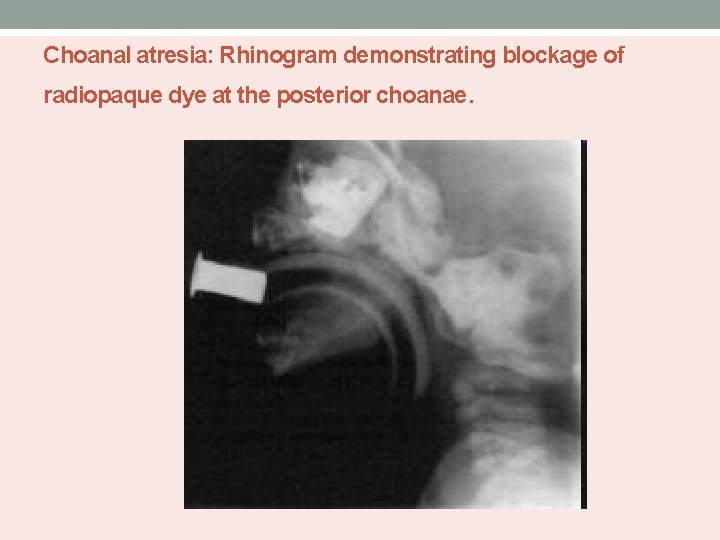

Choanal atresia: Rhinogram demonstrating blockage of radiopaque dye at the posterior choanae.